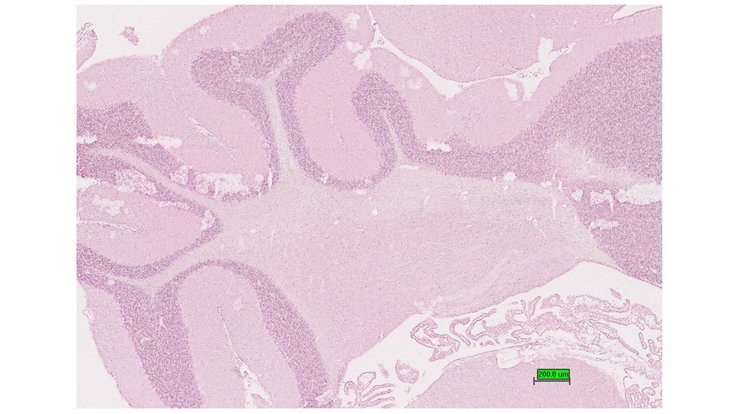

TS28: cerebellum Present UC Davis_1888633

Specimen UC Davis_1888634: postnatal adult; Pms1tm1.1(KOMP)Vlcg/Pms1+ (more )

Structure Level Pattern Image Note

TS28: cerebellum Present UC Davis_1888634